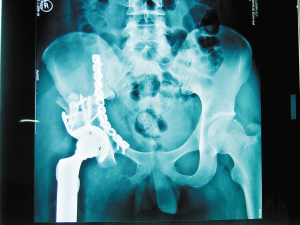

55岁女子车祸骨盆骨折手术后像没事人仅腰上两个小口子

头条团队的力量市一院成功开展高难度半骨盆置换术